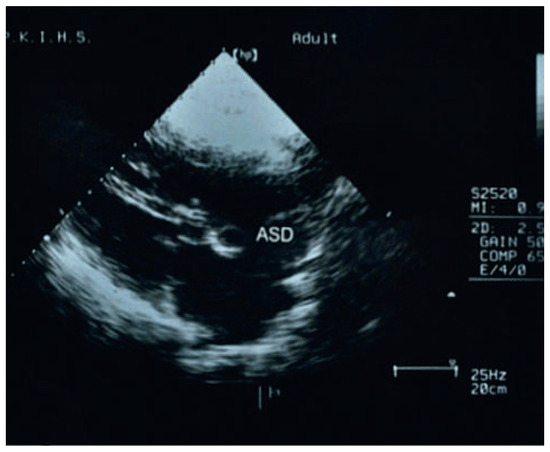

A Family with Upper Limb Malformations and Dyspnoea–The Holt-Oram Syndrome

Case report